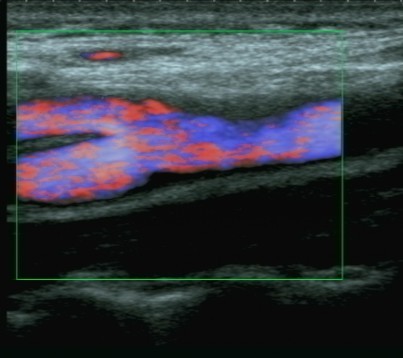

Oltre all'ecografia gastrointestinale, l'ecografia tiroidea rappresenta un altro campo specialistico di vasta esperienza con esecuzione della diagnostica base, il colordoppler e doppler tiroide e lo studio elastografico delle lesioni nodulari tiroidee altrimenti detta elastografia. Questa metodica permtte lo studio della elasticità dei tessuti e considerando che i tessuti neoplastici tendono ad essera di consistenza aumantata, l'elastografica ci aiuta a selezionare i noduli da sottoporre ad campionamento citologico con FNAB.